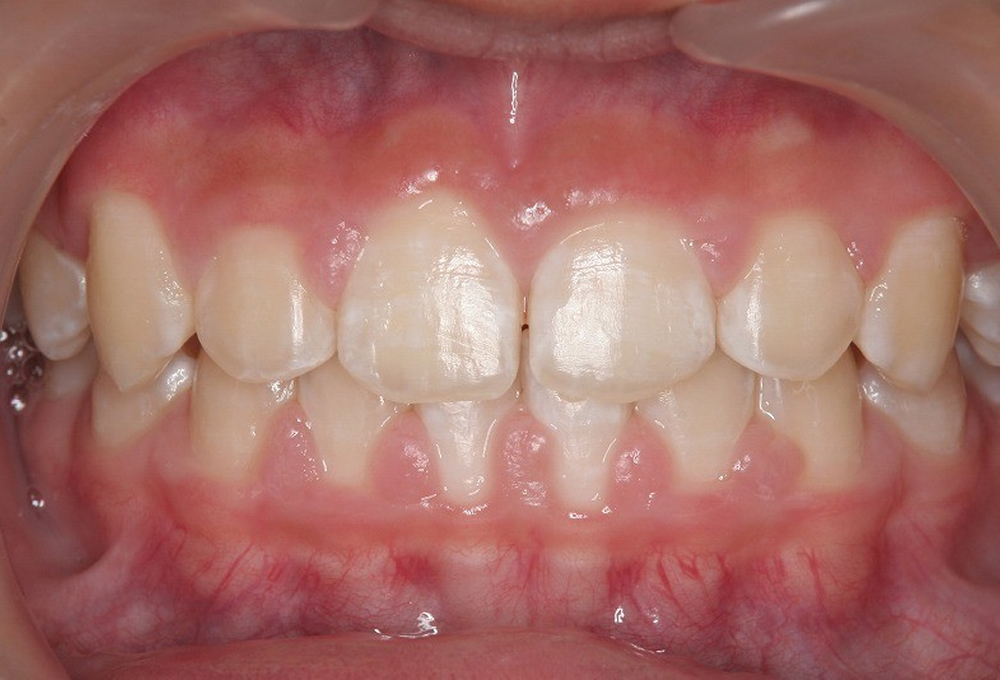

⑥術後 ホワイトニング後セラミックにて修復